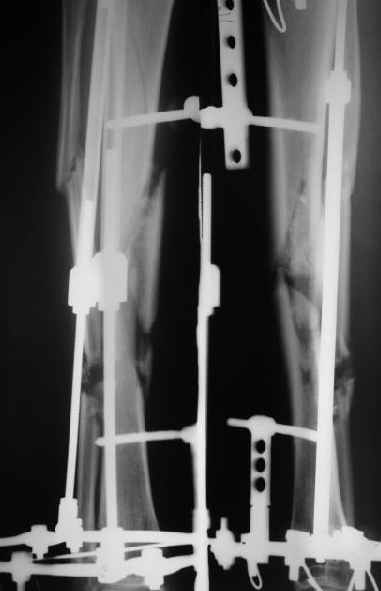

Диагноз: двойной оскольчатый перелом правого бедра в с/3 и н/3 со смещением, открытый оскольчатый перелом правой большеберцовой кости в с/3 со смещением двойной перелом малоберцовой кости. Оперирован проведена открытая репозиция, остеосинтез двумя пластинами бедренной кости, иммобилизация кокситной повязкой. На контрольных рентгенограммах от 21 01 04 имеется: несостоятельность остеосинтеза бедренной кости в в/3 выраженная угловая деформация; консолидирующийся перелом большеберцовой кости со смещением по длинне и выраженной вальгусной деформацией. Родственникам рекомендовали оперативное лечение. Больного доставят на осмотр 28.01.04, обдумываем способы лечения. Оперативное лечение планируем в два этапа, вначале на бедре, затем на голени. На бедре- удаляем верхнюю пластину, проводим остеотомию по линии верхнего перелома, проводим репозицию, остеосинтез пластиной с фиксацией верхнего, среднего и нижнего фрагментов.На голени-мнения разделились:- можно наложить аппарат внешней фиксации на голень, провести остеотомию б/берцовой кости в зоне перелома между проксимальным отломком и осколком, остеотомию малоберцовой кости, провести постепенную репозицию, тибиализацию (рисунок 3).-или провести остеотомию по линии перелома большеберцовой кости, репонировать и фиксировать пластиной. Новосибирская областьг Куйбышев ЦРБСергей Зырянов

Как я уже сообщал, пациент поступил к нам в пятницу на прошлой неделе.

Ко всему прочему у него еще и разгибательная контрактура коленного сустава - амплитуда градусов 15.

Сегодня сделана операция. Из бедра минимально инвазивно удалены пластинки. Один винт на верхней пластинке оказался сломан, так что пришлось там сделать разрезик побольше, см 5.

Хотя и с трудом, но на бедре удалось сразу выполнить закрытый интрамедуллярный остеосинтез с минимальным рассверливанием.

Редрессацию колена даже пытаться делать не стали.

На голени - чрескожная остеотомия малоберцовой кости, закрытая остеоклазия большеберцовой, дистракционный остеосинтез аппаратом.

В плане - востановление длины и оси голени, разработка движеий в колене. Не уверен, что удастся синтезировать голень стержнем при таком маленьком сгибании в коленном суставе.